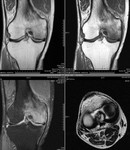

■[画像診断]膝関節の特発性骨壊死、軟骨下骨不全骨折について

・大腿骨内側顆の加重面 ←→ 離断性骨軟骨損傷との鑑別

・高齢女性、中高年男性(軟骨下骨不全骨折)

<MRI>

・骨壊死の超早期病変を描出可能

・壊死部はT1WI低信号。関節軟骨と軟骨下骨の欠損、変形

・(軟骨下骨不全骨折) 発症時、軟骨下骨にレンズ状の低信号域、その周囲に骨髄浮腫 → 浮腫減弱、嚢胞形成 → 皮質の陥凹

症例は、膝痛を訴える高齢男性。

MRIにて、大腿骨内側顆の加重面、軟骨下骨に線状低信号域あり、その周囲に広範な骨髄浮腫を認める。

軟骨下骨不全骨折/特発性骨壊死、と考えられた。